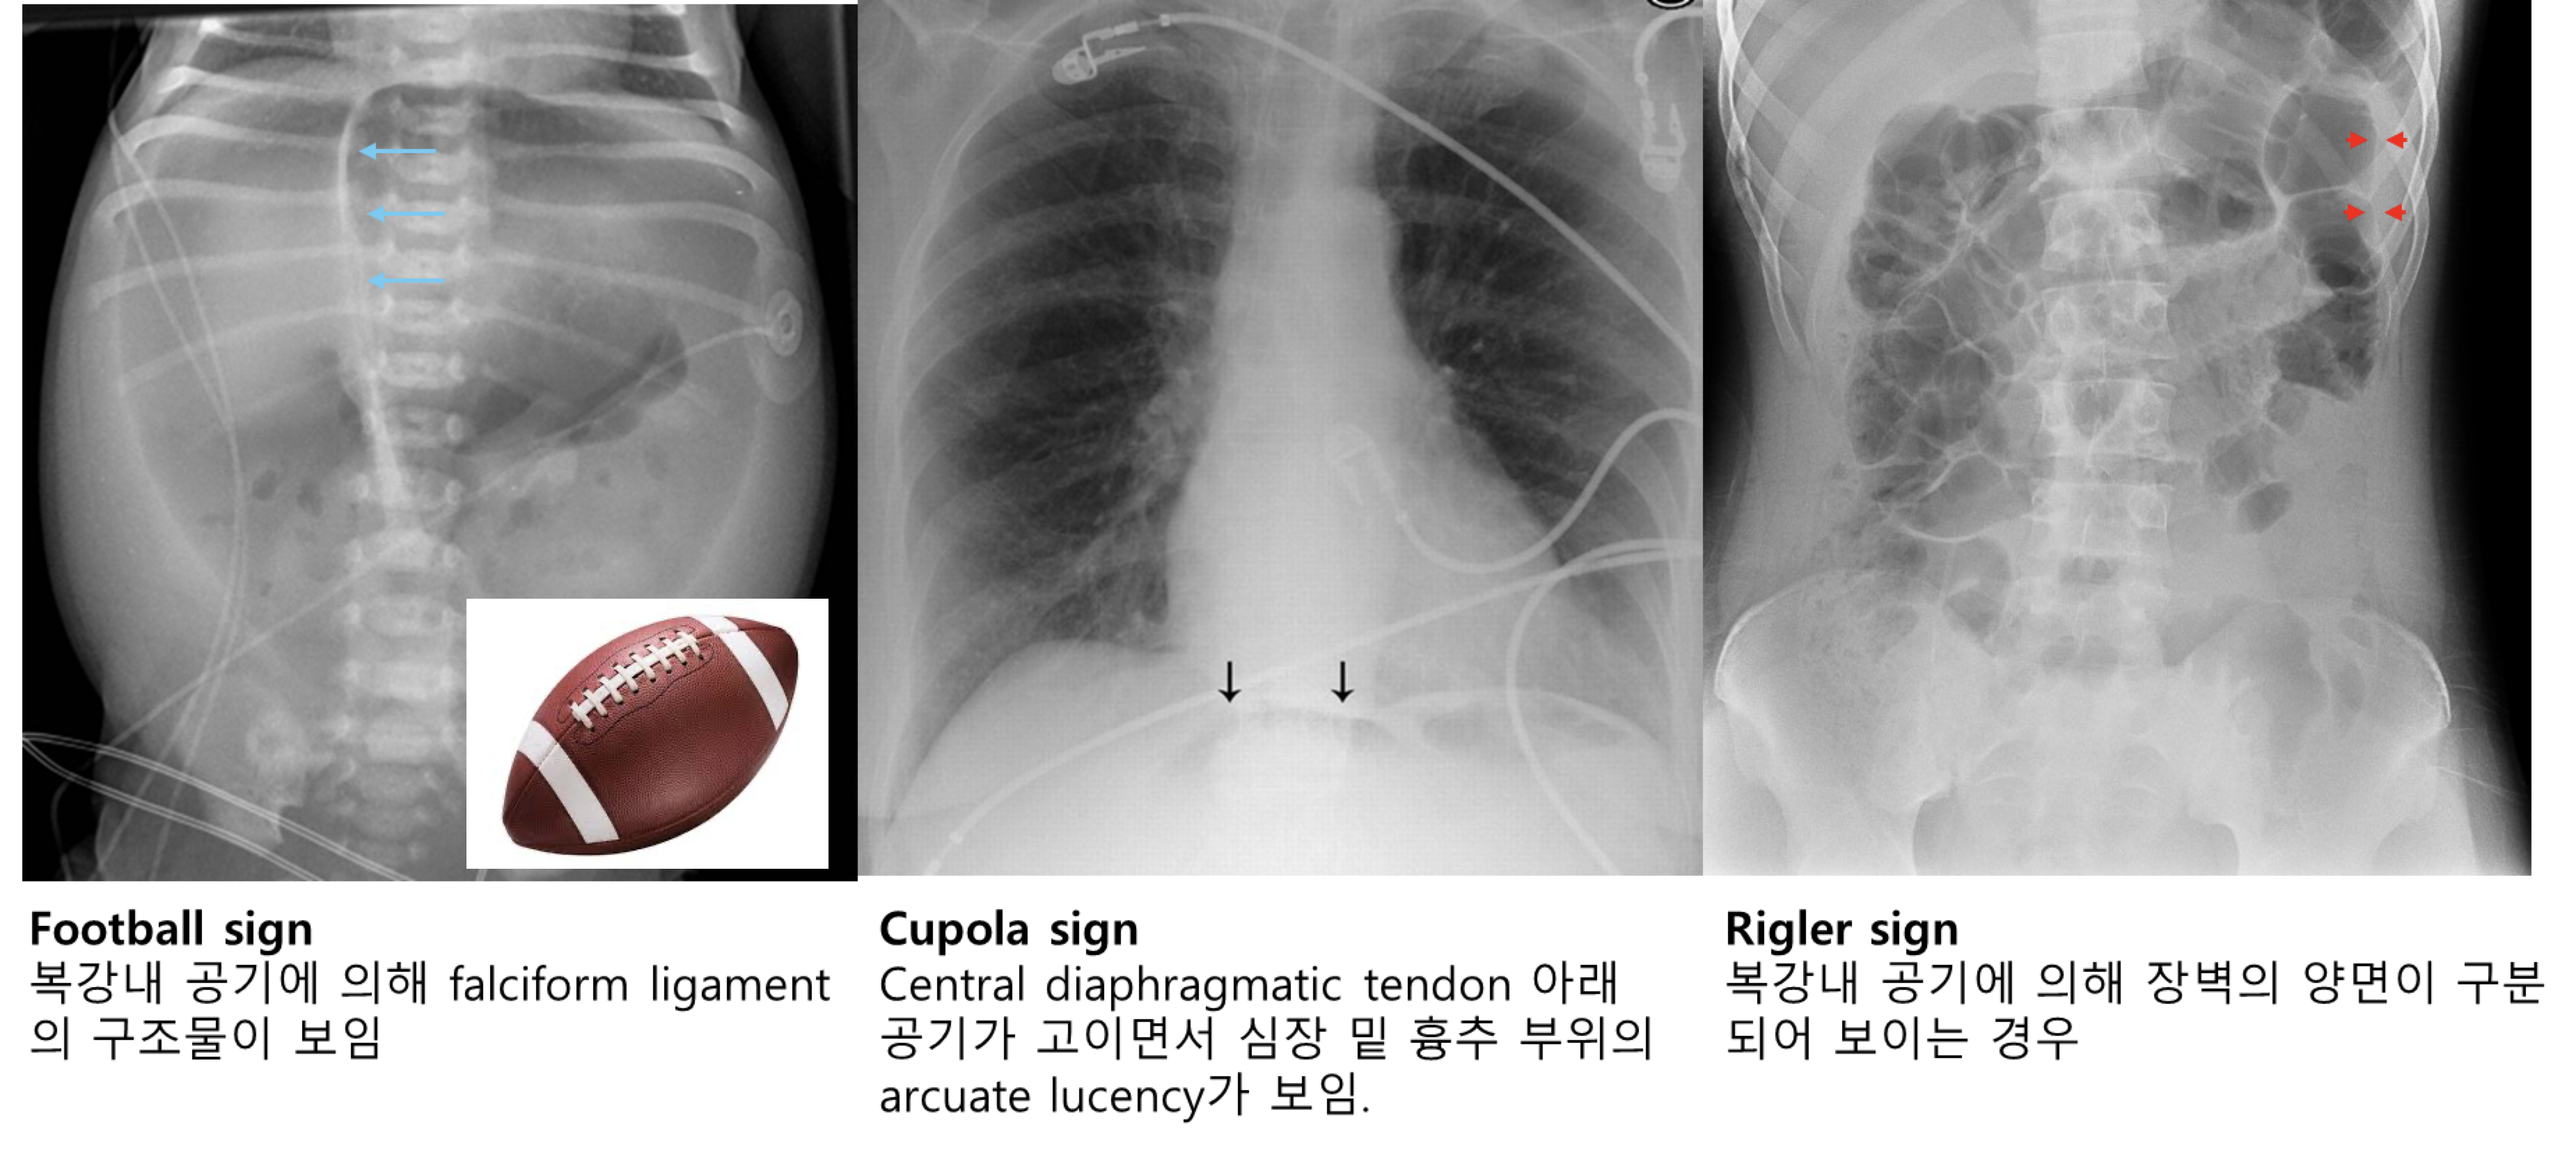

** AP abdomen 뿐 아니라, cross table lateral 또는 lateral decubitus 까지 촬영해서 기복증 여부를 반드시 평가

• 장벽 내 공기증 (Pneumatosis intestinalis): 가장 특징적인 소견

• 문맥 내 가스 (Portal venous gas): 중증 소견

• 기복증 (Pneumoperitoneum): 장 천공을 시사하는 소견 ('football sign' 등)

• pneumoperitoneum